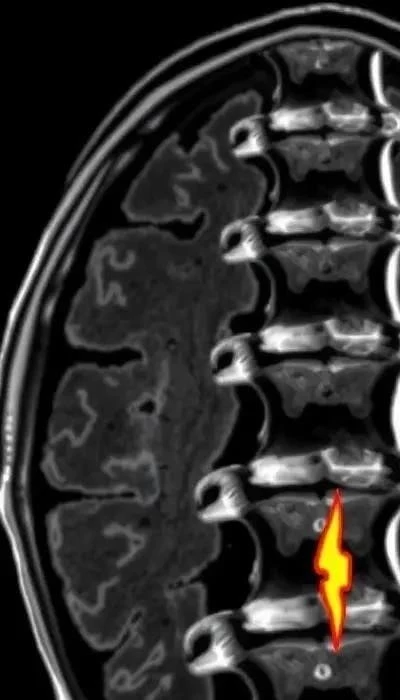

Уровни повреждения спинного мозга определяются по сегментам позвоночника: шейный (C1-C8), грудной (T1-T12), поясничный (L1-L5) и крестцовый (S1-S5). Уровень повреждения напрямую влияет на функциональные нарушения. Повреждения шейного отдела часто приводят к тетраплегии (параличу всех четырех конечностей), в то время как повреждения поясничного отдела обычно вызывают параплегию (паралич нижних конечностей).

Центромедуллярный синдром часто возникает при повреждениях шейного отдела и характеризуется слабостью в руках и потере чувствительности к боли и температуре. Синдром конуса возникает при повреждении conus medullaris и проявляется нарушением функции тазовых органов и слабостью в ногах. Синдром конского хвоста – повреждение нервных корешков в области поясничного отдела, вызывающее боль, слабость и нарушение функции тазовых органов.